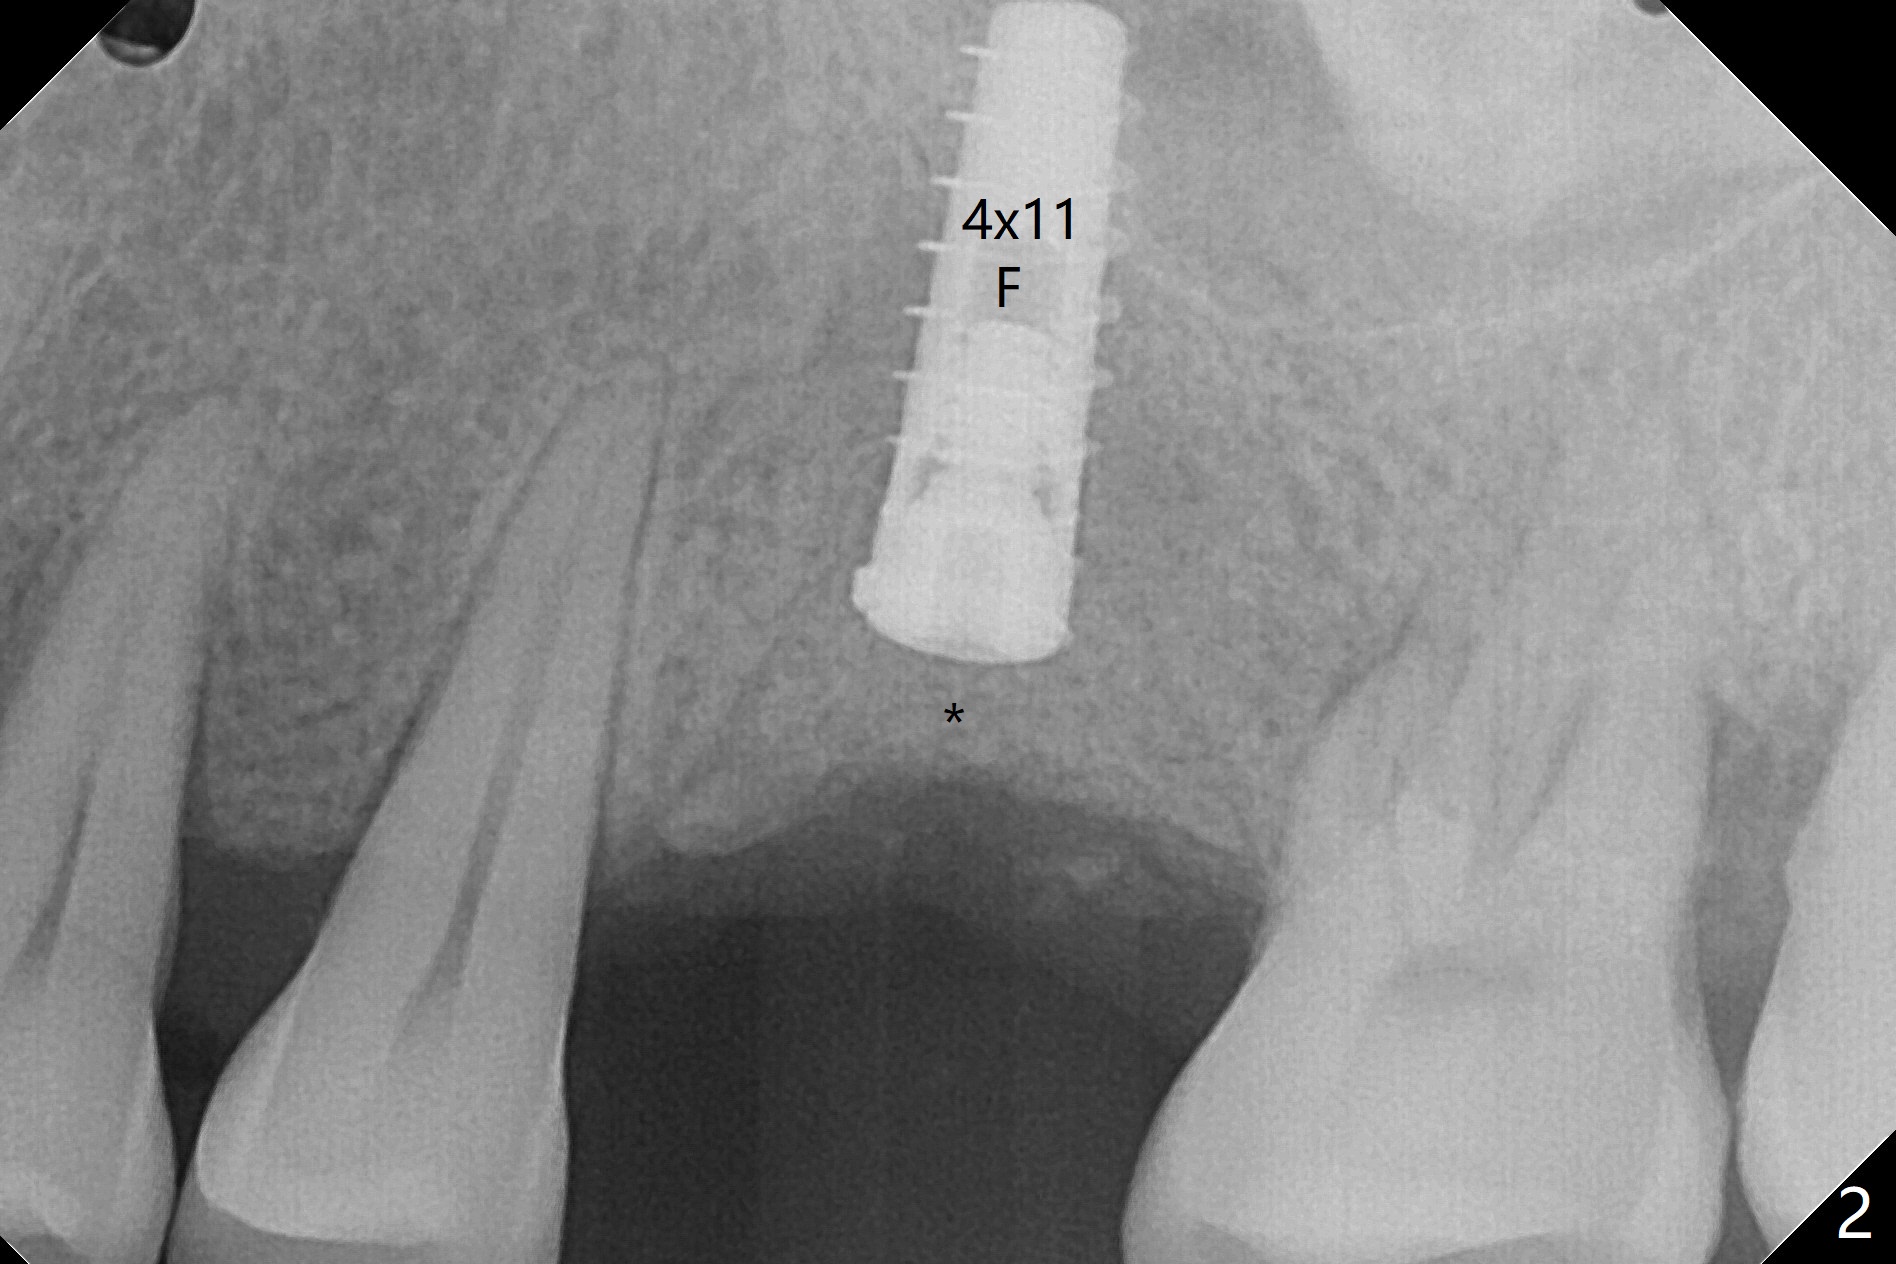

Nearly 4 months post implant exfoliation, the ridge at #14 looks narrow. Incision reveals loss of the palatal plate coronally. The same guide is used to finish osteotomy with modification. There are several points of difference. The 1st one is use of the guide for the complete procedure, including the implant placement so that there would be no apparent trajectory deviation. A bone-level implant is used instead of a tissue-level one. When a 4x11 mm dummy implant is ~1.5 mm shy of the depth (Fig.1 D), the palatal threads are exposed. To reduce further exposure, the final/definitive implant remains 4.0 mm in diameter instead of 4.5 mm as designed, followed by sticky bone, particularly palatal (Fig.2,3 *). In fact the implant is placed deeper than the failed one, relative to the sinus floor (Fig.4 (sinus lift without bone graft)). In fact the implant is placed deeper (Fig.4 (4x11 mm bone-level) than the failed one (Fig.5 (same magnification; 4.5x14 mm tissue-level)), relative to the sinus floor (yellow line).